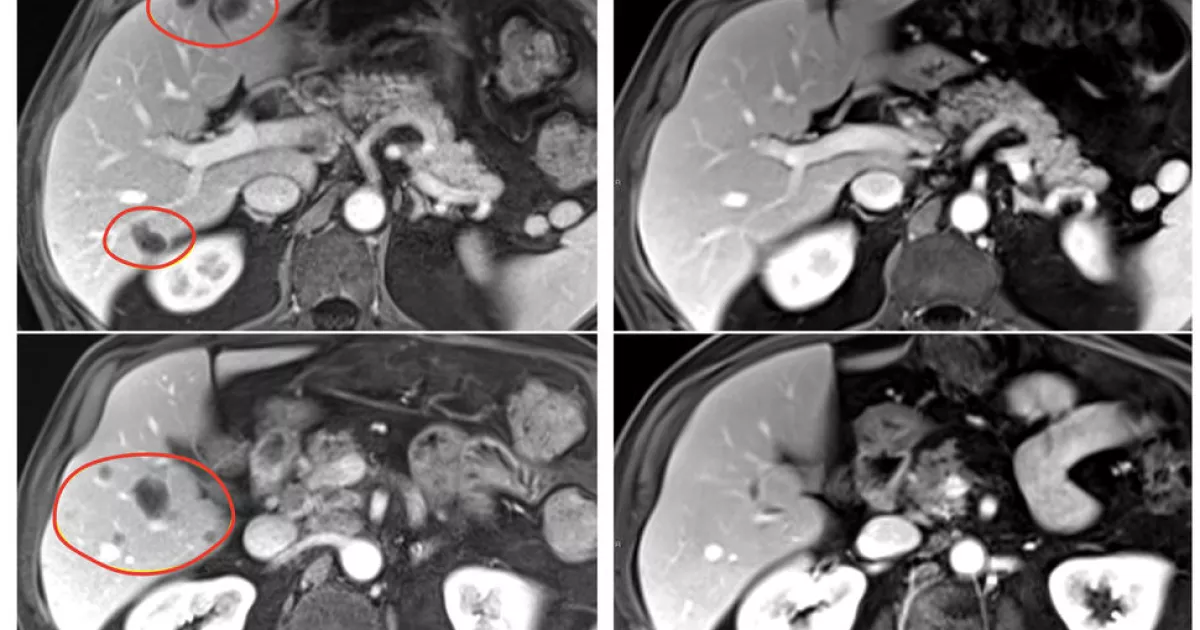

Patients in the clinical trial, who had a variety of gastrointestinal tumors, also received the immune checkpoint inhibitor pembrolizumab (Keytruda) to help further boost their immune response. The result was nearly 24% of patients treated with selected TILs plus pembrolizumab had a substantial reduction in the size of their tumors, compared with 7.7% of patients who received selected TILs without pembrolizumab. Patients treated with TILs that had not been selected for anti-tumor activity had no tumor shrinkage.

The clinical trial included 91 patients with metastatic gastrointestinal cancers — including esophageal, stomach, pancreatic, colon, and rectal cancers — that had worsened despite a median of four prior treatment regimens. In the pilot phase of the trial, 18 patients were treated with TILs that had not been selected for anti-tumor activity, and there were no objective responses (tumor shrinkage of at least 30% is considered an objective response). In the second phase, 39 patients were treated with selected TIL therapy, and three (7.7%) had objective responses.

In the third phase, 34 patients received pembrolizumab immediately before selected TIL therapy to prevent the newly introduced immune cells from becoming inactivated by the patient’s own immune system. This group had the best response, with 8 of 34 (23.5%) patients experiencing an objective response. All 91 patients had also received standard chemotherapy and high-dose interleukin-2 before the TIL therapy.

In the trial’s second and third phases, objective responses were seen in multiple types of gastrointestinal cancers, including cancers of the colon, rectum, pancreas, and bile duct. Responses lasted between 8 months and more than 5.8 years in the group that received selected TIL therapy alone, and between 4 months and 3.5 years in the group that received selected TIL therapy and pembrolizumab. Serious side effects occurred in 30% of patients treated with selected TILs.